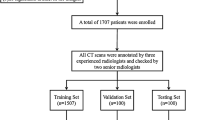

A deep learning model was constructed from 2987 training images and 1298 validation images, which were obtained from post-processing of the image fusion between X-ray images of normal post-operative radiography and surgical sponge. Then, another 800 images were used, i.e., 400 with and 400 without surgical sponge. The detection characteristics of retained sponges between the model and a general observer with 10-year clinical experience were analyzed using the receiver operator characteristics.